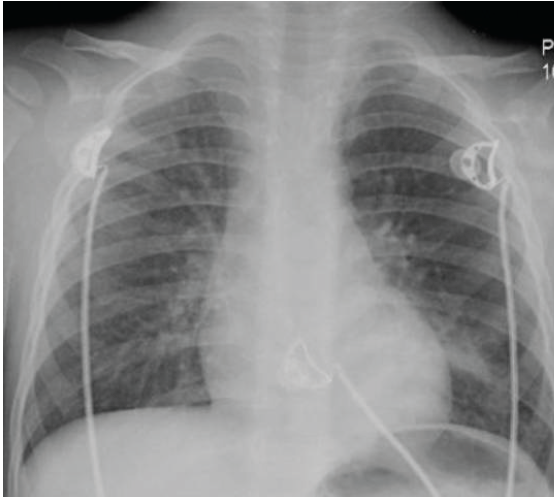

Foreign-Body Ingestion

Nishit Patel, MD; Bashar Shihabuddin, MD

We present 2 cases that highlight the importance of eliciting a choking history in any child presenting with respiratory symptoms.